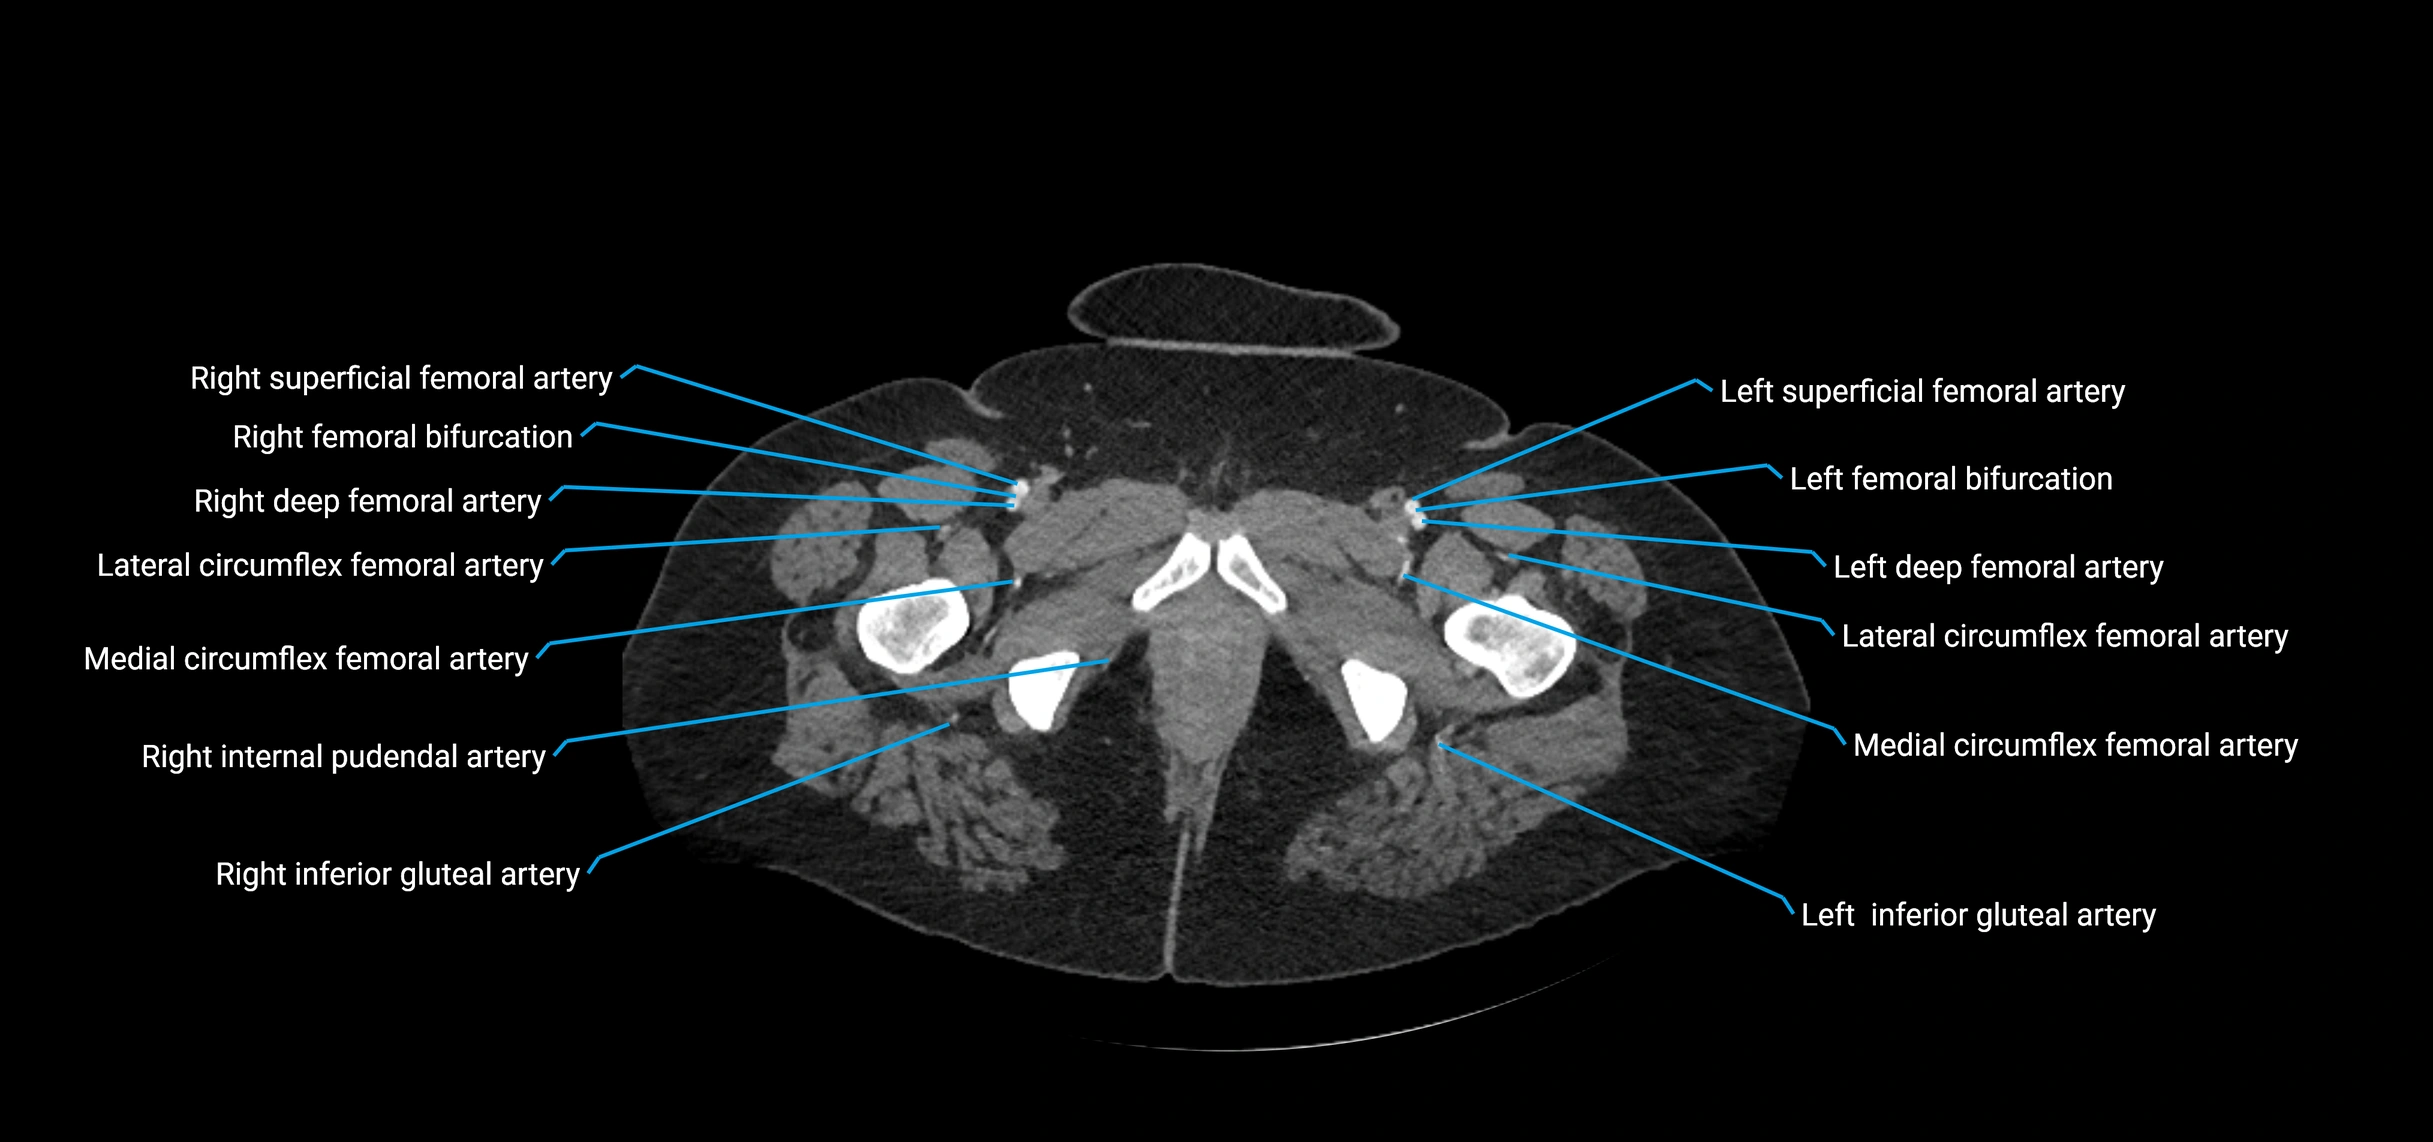

CT images

image

Contrast-enhanced CT (CTA):

• Gold standard for abdominal aortic imaging

• Provides excellent detail of lumen, wall, aneurysm, thrombus, and branch vessels

• Multiplanar and 3D reconstructions help in aneurysm measurement, stent graft planning, and dissection evaluation

• Detects acute rupture, traumatic injury, or occlusion with high sensitivity